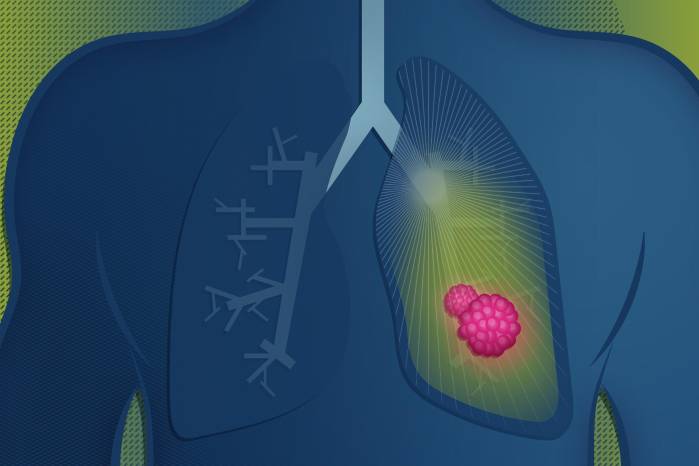

Sus síntomas son tos persistente, dificultad para respirar, dolor en el pecho, cansancio extremo o pérdida de peso, y suelen confundirse con afecciones respiratorias comunes. Como resultado, el 85 % de los casos se detecta en etapas avanzadas, cuando las opciones terapéuticas son más limitadas y el pronóstico es menos favorable.

El diagnóstico incluye exámenes físicos, pruebas de laboratorio, estudios por imágenes y tamizaje, herramientas que permiten identificar la enfermedad en fases tempranas y mejorar la supervivencia. Sin embargo, el acceso oportuno a estas pruebas sigue siendo un reto.